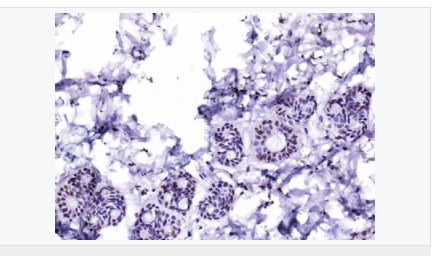

| 產(chǎn)品應用 | WB=1:500-2000 ELISA=1:5000-10000 IHC-P=1:100-500 IHC-F=1:100-500 Flow-Cyt=2ug/Test IF=1:100-500 (石蠟切片需做抗原修復) not yet tested in other applications. optimal dilutions/concentrations should be determined by the end user. |

| 免 疫 原 | KLH conjugated synthetic peptide derived from human CIDEC:101-200/238 |

| 產(chǎn)品介紹 | This gene encodes a member of the cell death-inducing DNA fragmentation factor-like effector family. Members of this family play important roles in apoptosis. The encoded protein promotes lipid droplet formation in adipocytes and may mediate adipocyte apoptosis. This gene is regulated by insulin and its expression is positively correlated with insulin sensitivity. Mutations in this gene may contribute to insulin resistant diabetes. A pseudogene of this gene is located on the short arm of chromosome 3. Alternatively spliced transcript variants that encode different isoforms have been observed for this gene. [provided by RefSeq, Dec 2010]. Tissue specificity: Expressed mainly in small intestine, heart, colon and stomach and, at lower levels, in brain, kidney and liver. Function: May act as a CEBPB coactivator in white adipose tissueto control the expression of a subset of CEBPB downstream targetgenes, including SOCS1, SOCS3, TGFB1, TGFBR1, ID2 and XDH (Bysimilarity). Binds to lipid droplets and regulates theirenlargement, thereby restricting lipolysis and favoring storage. Atfocal contact sites between lipid droplets, promotes directionalnet neutral lipid transfer from the smaller to larger lipiddroplets. The transfer direction may be driven by the internalpressure difference between the contacting lipid droplet pair. Whenoverexpressed in preadipocytes, induces apoptosis or increases cellsusceptibility to apoptosis induced by serum deprivation or TGFBtreatment. As mature adipocytes, that express high CIDEC levels,are quite resistant to apoptotic stimuli, the physiologicalsignificance of its role in apoptosis is unclear. Subunit: Interacts with CEBPB (By similarity). Interacts withCIDEA. Subcellular Location: Nucleus (By similarity). Endoplasmicreticulum (By similarity). Lipid droplet. Note=Diffuses quickly onlipid droplet surface, but becomes trapped and clustered at lipiddroplet contact sites, thereby enabling its rapid enrichment atlipid droplet contact sites. Tissue Specificity: Expressed mainly in adipose tissue, smallintestine, heart, colon and stomach and, at lower levels, in brain,kidney and liver. Post-translational modifications: Ubiquitinated and targeted to proteasomal degradation,resulting in a short half-life. Protein stability depends ontriaclyglycerol synthesis, fatty acid availability and lipiddroplet formation (By similarity). DISEASE: Note=In omental adipose tissue of obese patients matchedfor BMI, expression levels tend to correlate with insulinsensitivity. Expression is increased 2-3 fold in the group ofpatients with high insulin sensitivity, compared to theinsulin-resistant group. This observation is consistent with theidea that triglyceride storage in adipocytes plays an importantrole in sequestering triglycerides and fatty acids away from thecirculation and peripheral tissues, thus enhancing insulinsensitivity in liver and muscle. This effect is not significant insubcutaneous adipose tissue (PubMed:18509062). In subcutaneousadipose tissue of diabetic patients, tends to negatively correlatewith body mass index and total fat mass, independently of insulinsensitivity (PubMed:18334488). Similarity: Contains 1 CIDE-N domain. SWISS: Q96AQ7 Gene ID: 63924 Database links: Entrez Gene: 63924 Human Entrez Gene: 14311 Mouse Omim: 612120 Human SwissProt: Q96AQ7 Human SwissProt: P56198 Mouse Unigene: 567562 Human Unigene: 635072 Human Unigene: 10026 Mouse Unigene: 33794 Rat Important Note: This product as supplied is intended for research use only, not for use in human, therapeutic or diagnostic applications. |